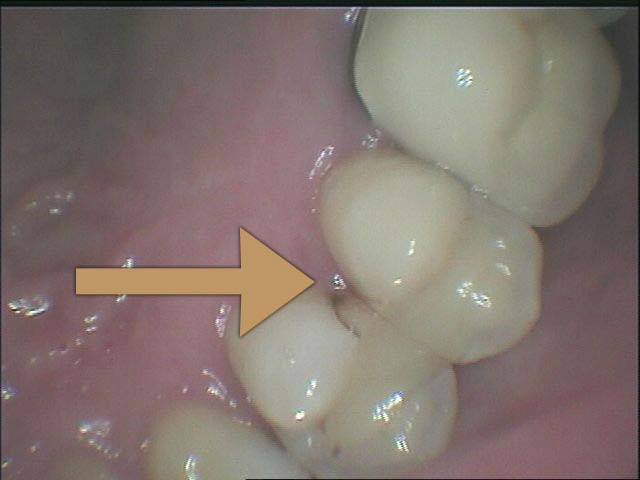

牙縫是一般患者發生蛀牙最易忽略的地方,因為難以被看見

但是樹酯因為強度不足往往一段時間後,產生邊緣龜裂,與二次蛀牙這時候蛀牙範圍往往會比第一次更大,可以使用3D齒雕作修復, 提供牙齒良好的強度與美觀。

圖2較大的蛀洞可使用3D齒雕,保存較多牙齒結構,並提供足夠強度的支撐,恢復牙齒型態與功能。